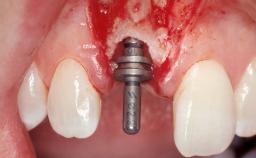

Immediate Placement of an Implant in a Maxillary Left Central Incisor Site

A 33-year-old female patient presented with an upper left central incisor that required extraction after a failed endodontic therapy. The tooth had been traumatized when the patient was a teenager and had undergone several endodontic treatments, including two apicectomy procedures. The patient was in good health and did not smoke. Clinical examination showed that the patient had a high lip line. In full smile, the gingival margins of the upper teeth were visible to the first molars. The gingival margins of central incisors 11 and 21 were only just showing. Examination of tooth 21 confirmed that the tooth was mobile and had hypererupted by 1 mm.

Placement Protocol Immediate implant placement

Socket Morphology Single-root socket

Socket Integrity Damage to one or more bone walls

Bone Volume Damage to one or more socket walls